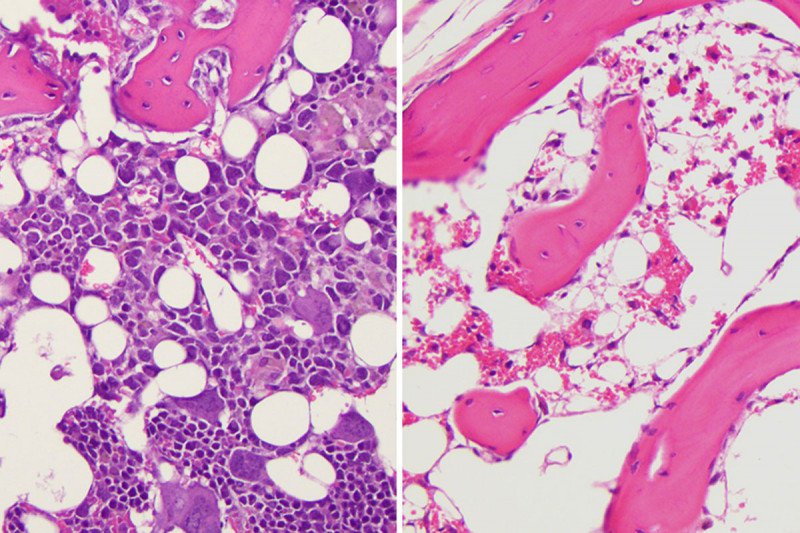

Bolstering fat cells offers potential new leukemia ...

Bolstering fat cells offers potential new leukemia ... from media.eurekalert.org

Several types of cancer, including multiple myeloma, leukemia, and lymphoma, can develop in the bone marrow. Definition cancer is not just one disease, but a large group of almost 100 diseases. Bone marrow cancer includes leukemias and multiple myeloma. These procedures collect a sample of bone marrow. Our experts at upmc children's hospital of pittsburgh treat a range of genetic and acquired bone marrow failure disorders: In other blood cancers, the malignant cells spread to the marrow but do so only later in the disease, after getting their start in the lymph nodes or spleen, for instance. Bone marrow cancer bone marrow cancer is defined as the cancerous growth of cell or malignant cells which develop in the blood forming cells of the bone marrow which is the soft tissue in the center of the bones in the body. White blood cells, which can be granulocytes or lymphocytes , develop in the bone.